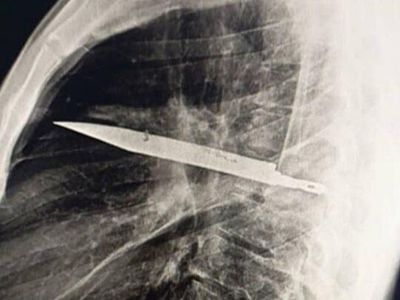

Foto-foto Penampakan Pisau Menancap di Dada, Pasien Sadar Setelah 8 Tahun

Begini penampakan pisau yang menancap di dada seorang pria di Tanzania. Pasien baru menyadari di tubuhnya ada pisau 8 tahun kemudian.